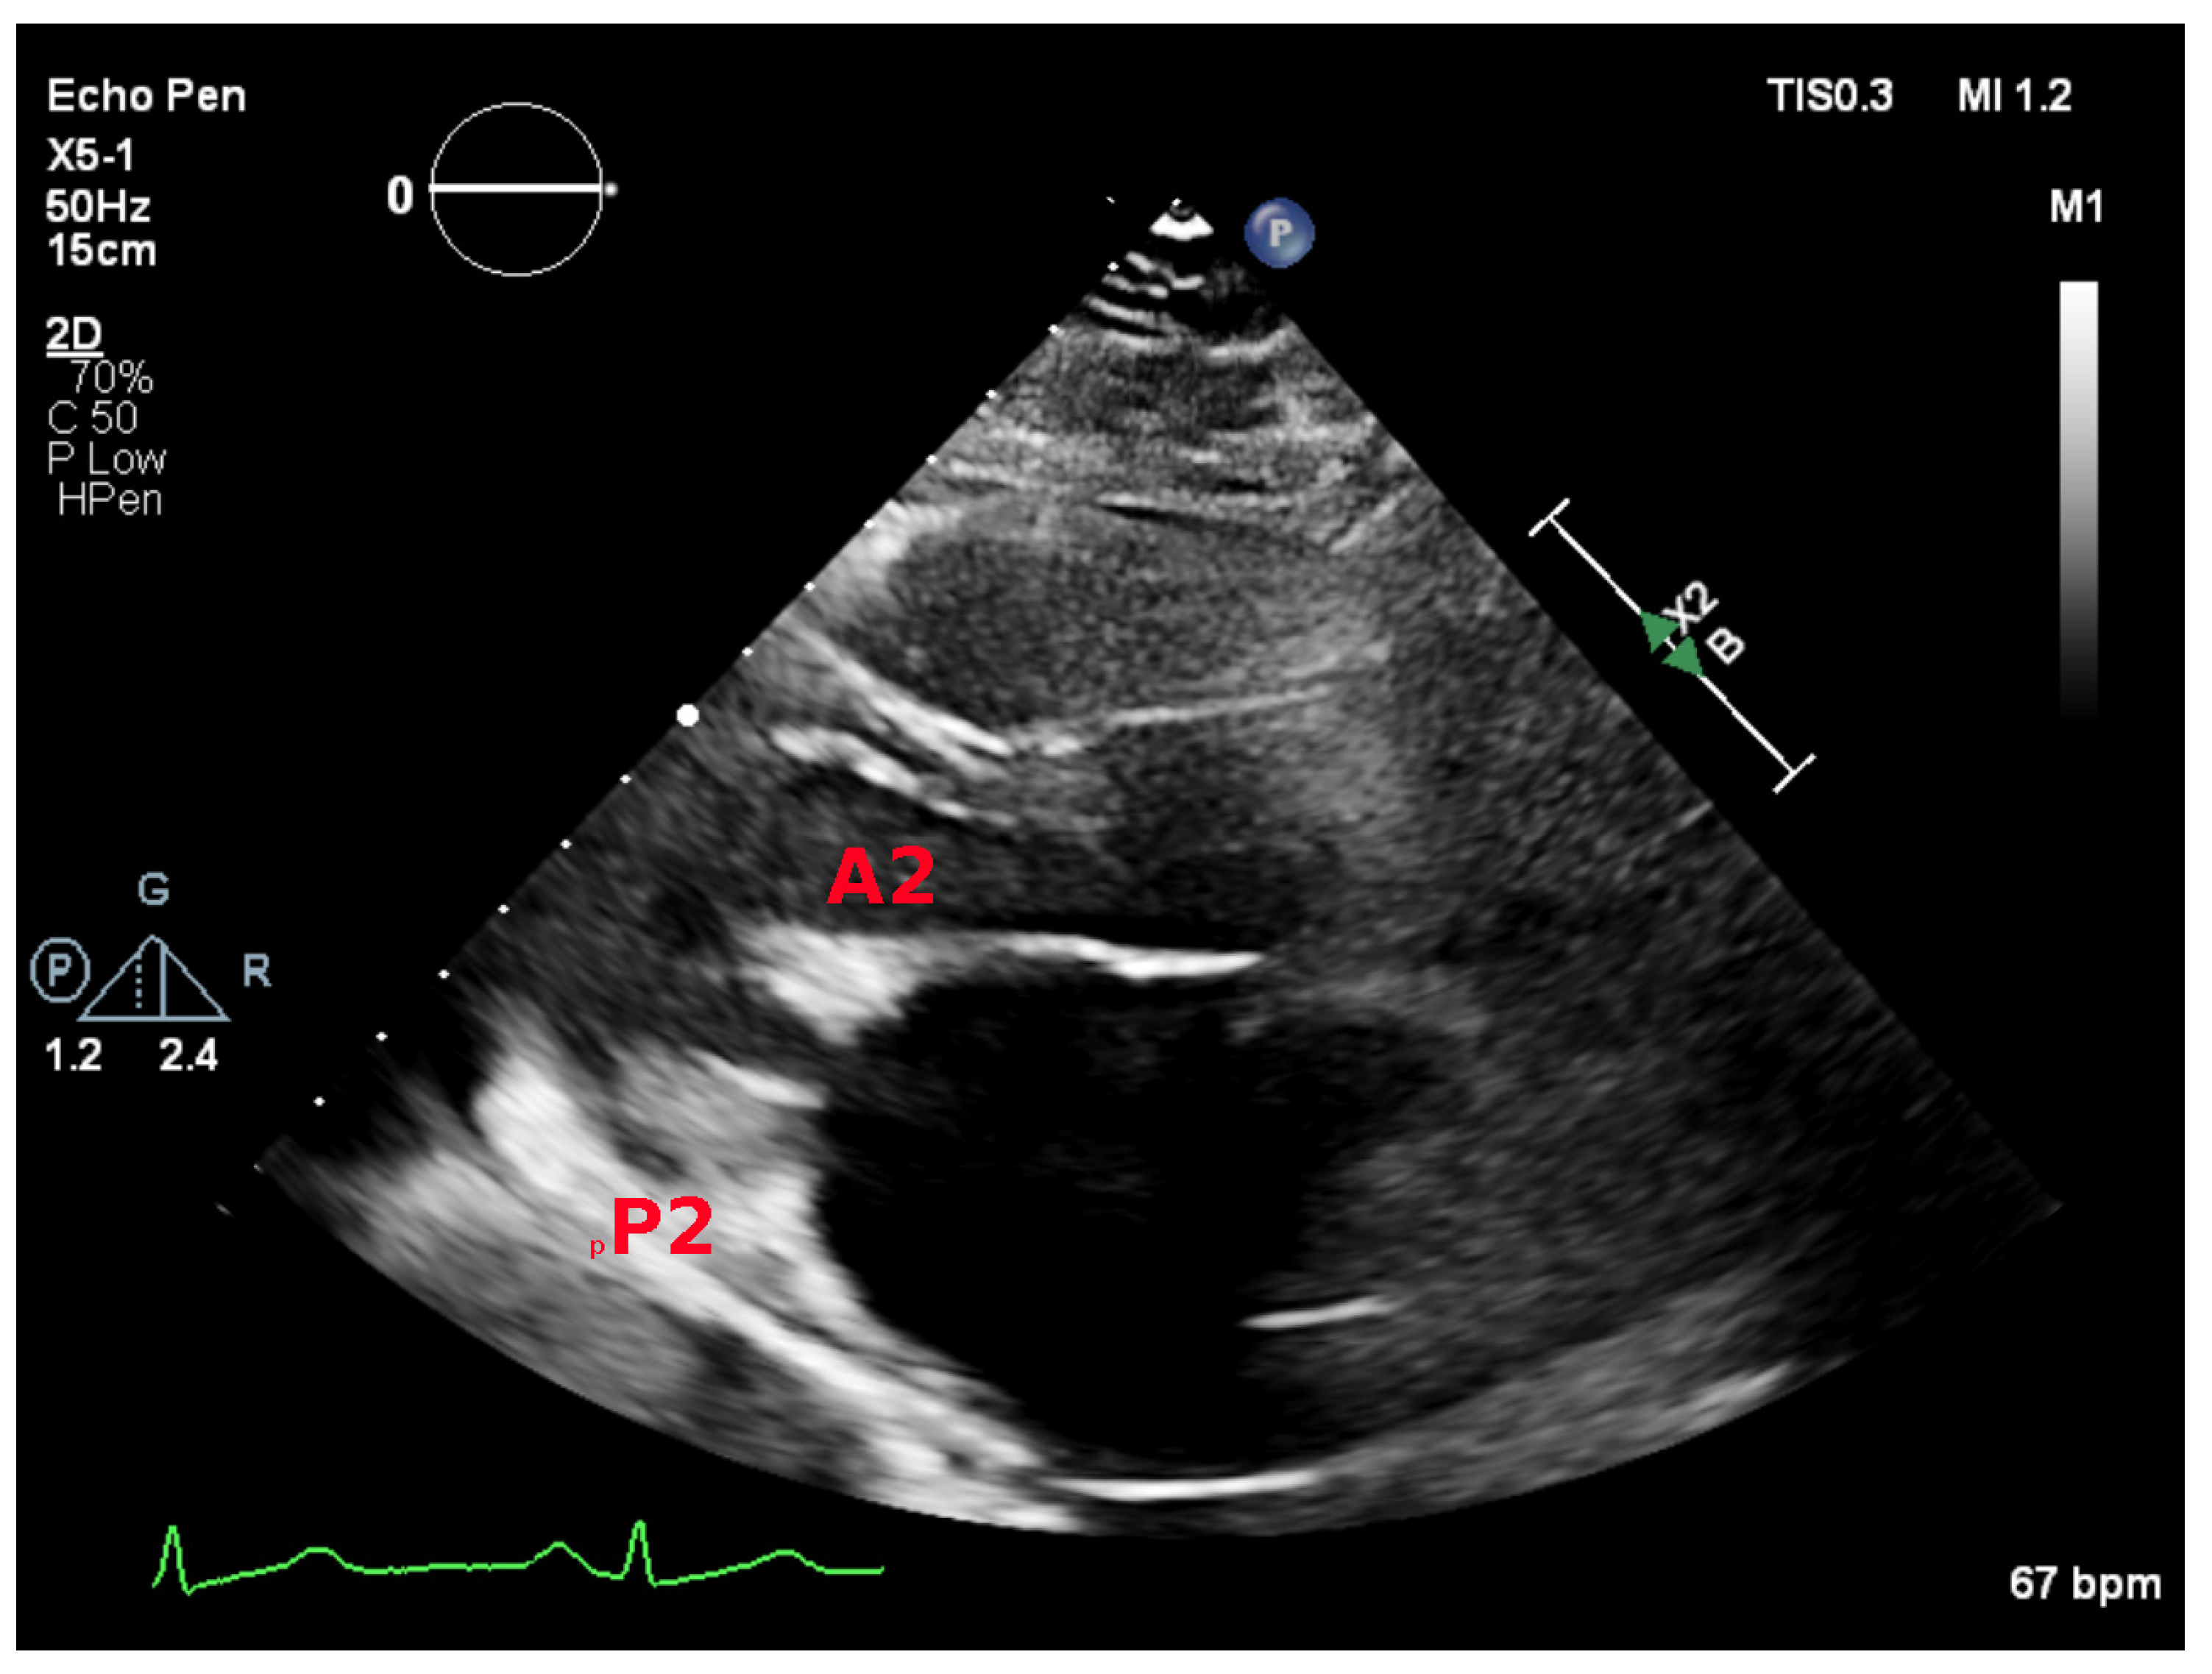

5.1. Parasternal Long-Axis View

5.2. Parasternal Short-Axis View